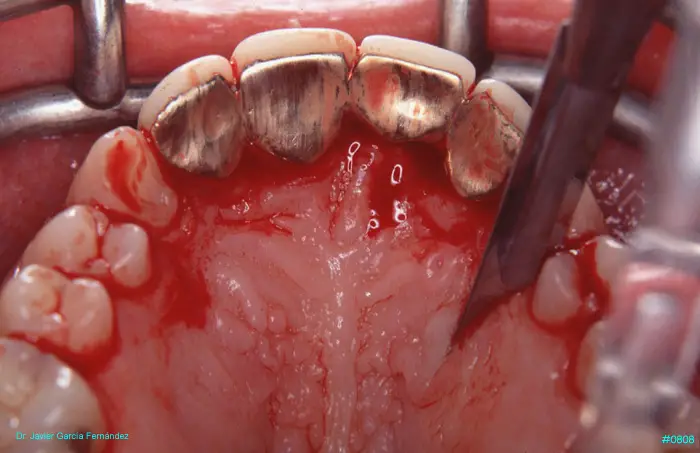

Atlas of Surgical Techniques in Periodontics. Chapter III. Atlas de Técnicas Quirúrgicas en Periodoncia